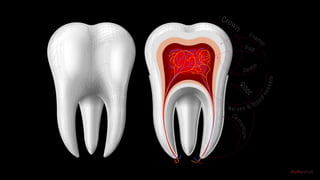

Unlike skin, teeth don’t heal

Unlike bone, teeth don’t heal